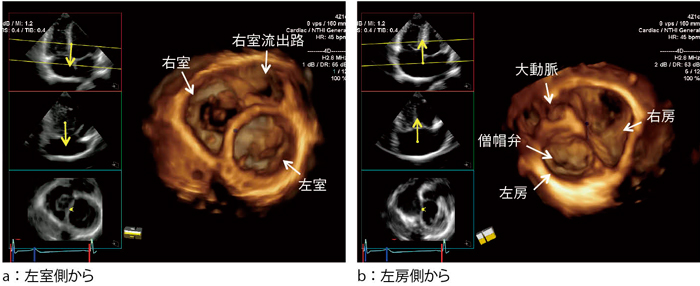

[A12295555]実践3D心エコー図法

実践3D心エコー図法【電子版】 | 医書.jp,さまざまな種類の心エコー検査「3D心エコー検査」 | VIEW Medical Gallery Site,3D心エコー:どうやって使えば手術に役立てられるか? 解剖学的評価を中心に,次世代のリアルタイム3D心エコー装置の開発-技術解説 - GEヘルスケア・ジャパン株式会社 - inNavi Suite,ACUSON SC2000」によるリアルタイムFull Volume Imagingの活用法 - 技術解説 - シーメンス・ジャパン株式会社 - inNavi Suite